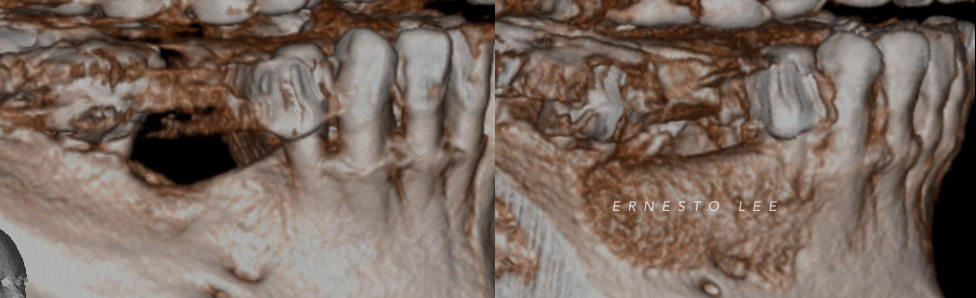

Patient suffered a traumatic injury at age 12. Five implants were placed during his early 20’s that subsequently failed. Implants were removed and repeated bone grafting procedures were unsuccessful, resulting in inadequate bone volume for implants and heavy scar formation. Patient was eventually referred to our office for augmentation of the severely maxillary anterior residual ridge.

S.M.A.R.T. VERTICAL & HORIZONTAL AUGMENTATION

Performed in a single office procedure using local anesthesia and two small incisions. No flaps, no tenting screws and no membranes were utilized. Sufficient horizontal and vertical bone volume was achieved to allow future placement of multiple implants.

Substantial vertical augmentation in the area of the failed anterior implants accomplished with the S.M.A.R.T. method.  The patient reported minimal pain and moderate swelling. Periosteal elevation was difficult due to extensive scar tissue.

Implants were placed 9 months following the S.M.A.R.T. bone graft. Bone in the vertically grafted areas was hard to drill through the osteotomy process. All implants exhibited excellent primary stability.